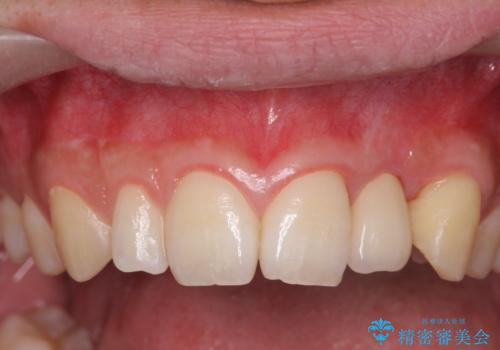

- 前歯の永久歯が元々なく、乳歯を失ったタイミングで前歯の審美性の回復を求めて来院されました。

機能・審美性の回復手段として、インプラント治療・ブリッジ・部分床義歯が考えられます。

それぞれの治療に特徴がありますが、取り外しの必要がなく隣の歯を削る必要も必要ないインプラント治療を選択されました。

前歯部にインプラントを埋入し、きれいに仕上げるためには骨の造成技術や歯肉の厚みを増すような処置を行い、インプラント周囲の環境を整備することが肝要です。